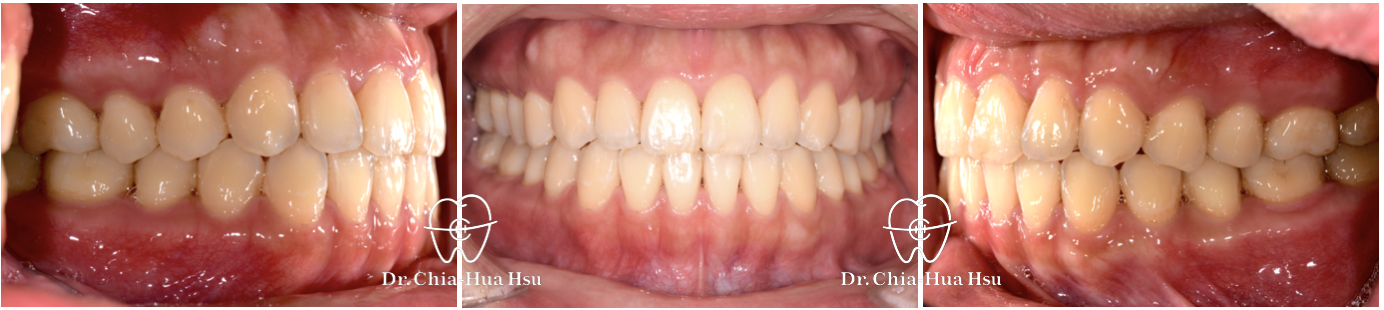

治療前

治療後

• 治療結果:咬合恢復正常,微笑曲線更自然!